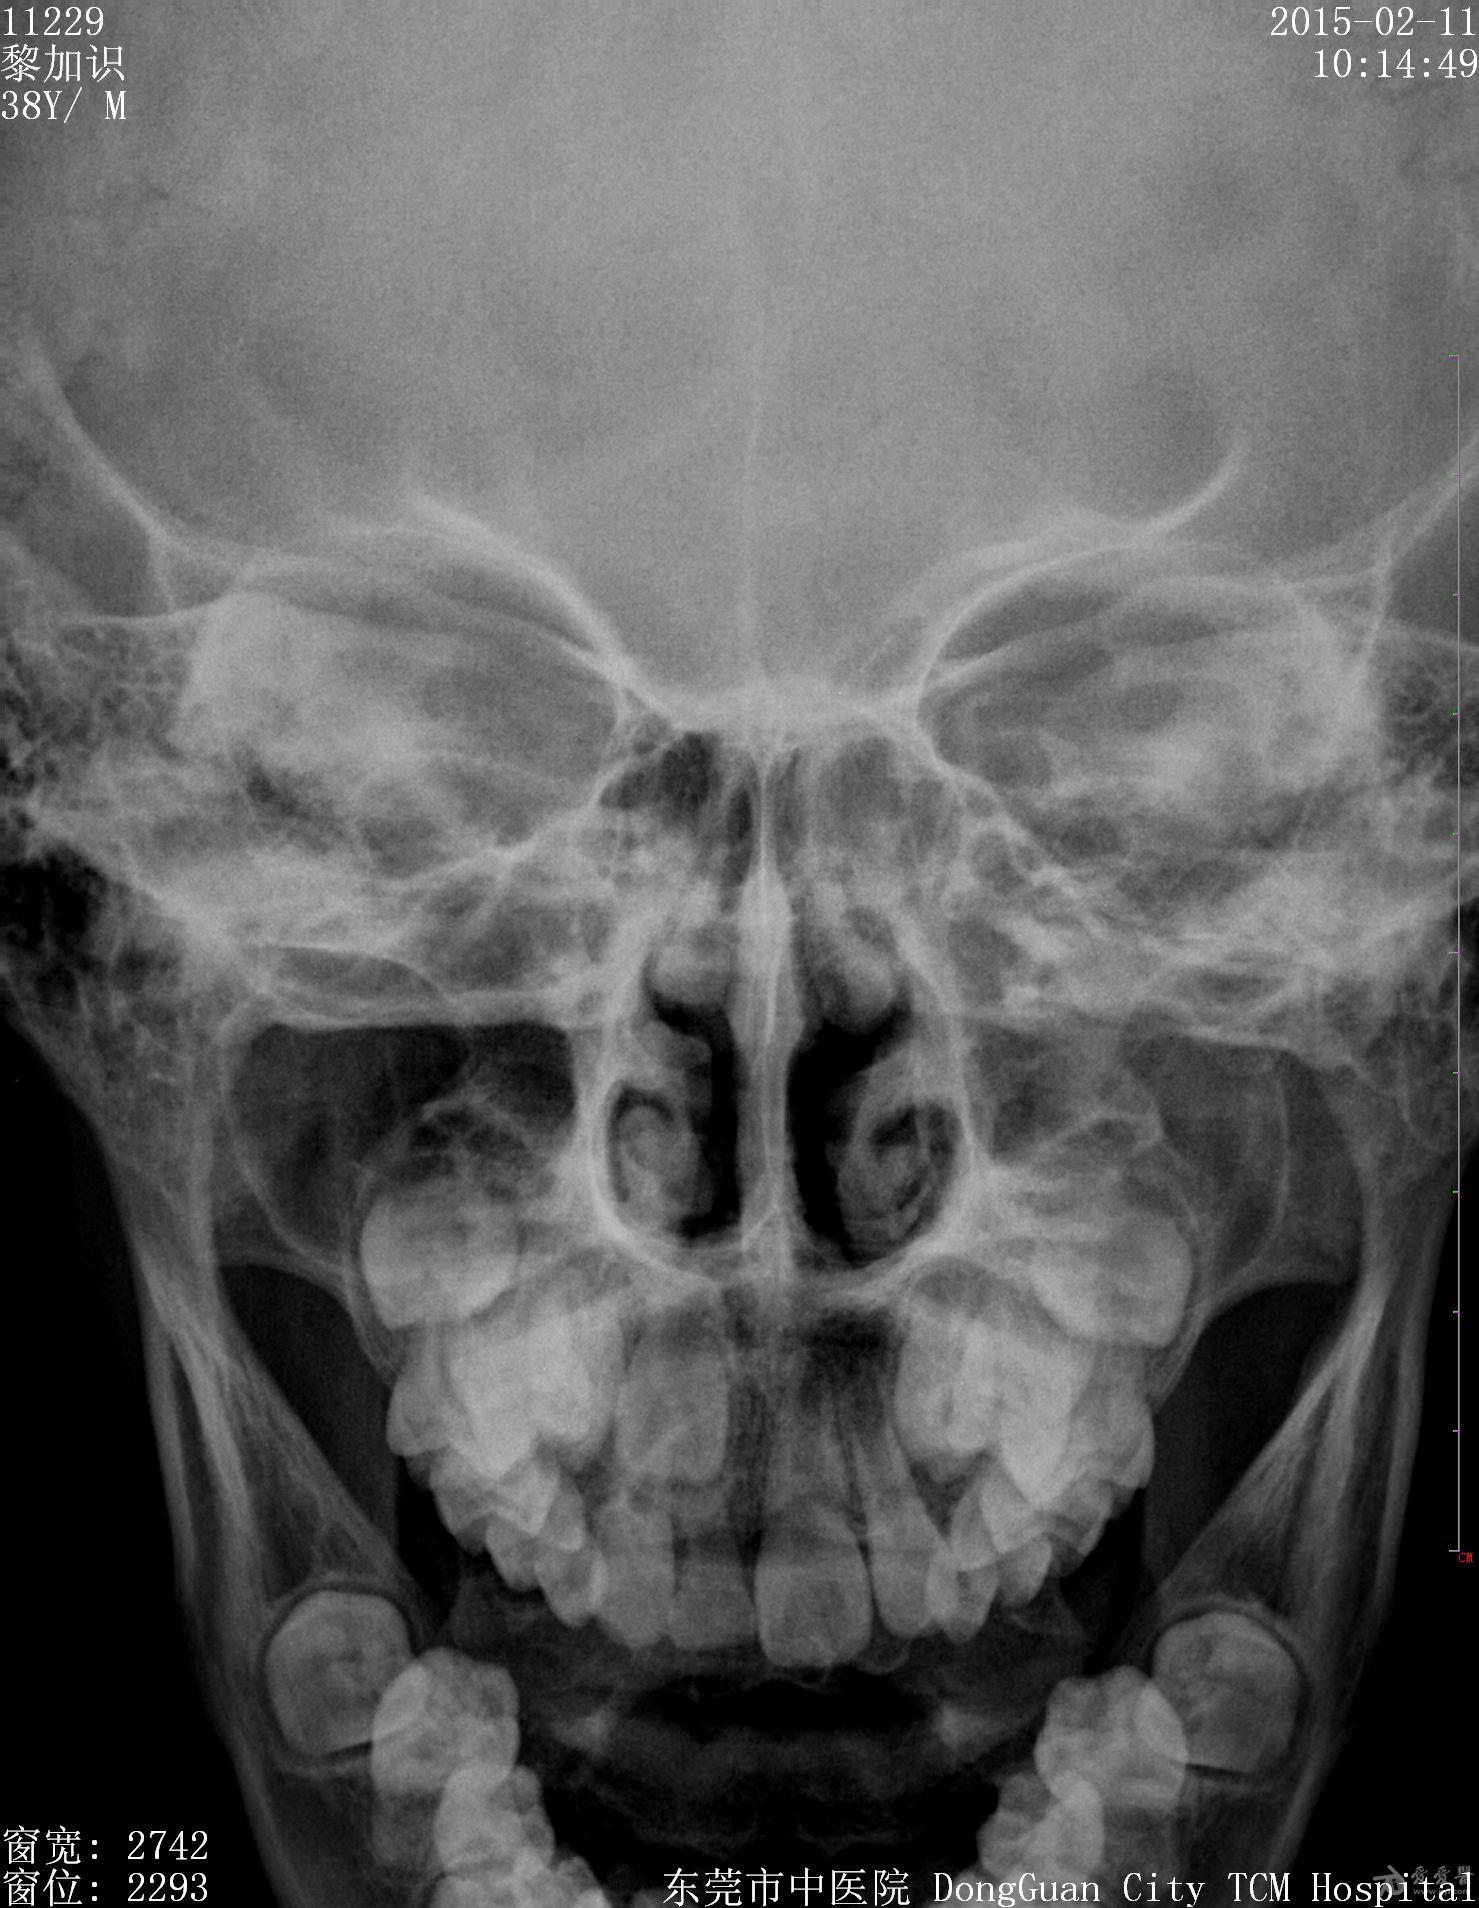

男,9岁10个月,右侧中切牙乳牙未换,右侧切牙已换。牙片显示右中切牙恒牙位置异常,与右侧切牙(恒牙)部分重叠,且右中切牙恒牙牙根稍短小(位置影响?),如何处理?能否矫正?

最好拍个**T确定恒牙位置,确定阻生的原因,再做处理!!